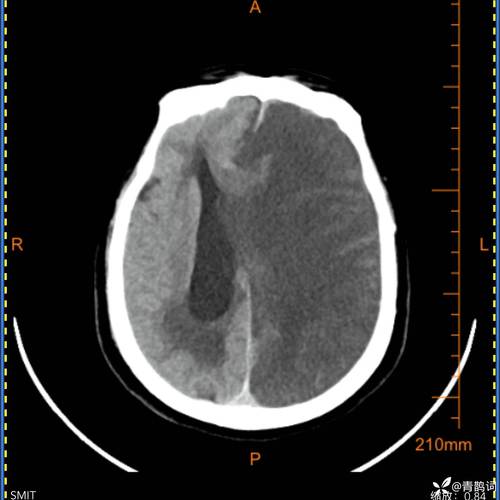

- 意识障碍:这是大面积脑梗最危险的表现,患者可能出现嗜睡、昏睡、甚至昏迷,因为大面积脑水肿会压迫脑干等生命中枢,影响呼吸和心跳。

- 颅高压症状:剧烈头痛、喷射性呕吐、血压升高等,这是因为梗死的脑组织肿胀,导致颅内压力急剧增高。

- 控制颅高压:使用高渗性脱水剂(如甘露醇)来减轻脑水肿,防止脑疝形成(这是致死的主要原因)。